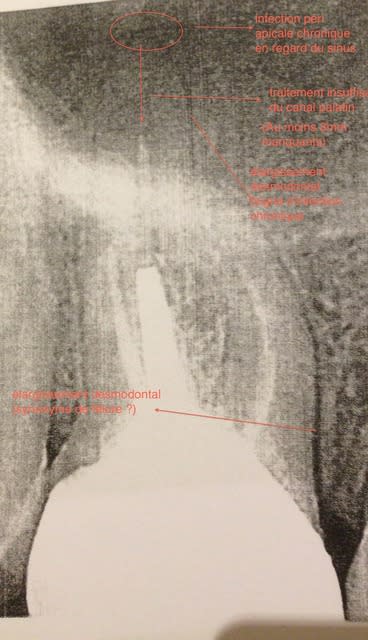

Il a affirmé à la patiente que j'ai fracturé moi-même cette dent en déposant l'inlay core, ce qui est improuvable

Il m'as aussi affirmé que je n'aurais pas du retraiter (et il s'est présenté comme expert auprès des tribunaux, une honte )

Hum, on voit rien.

Mais il voulait que tu extrais directement?